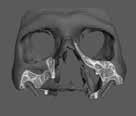

A diagnosztikai panoráma röntgenfelvételen a mandibula íve mérsékelt IIIIV. osztályú atrófiával és megfelelő térfogatú, viszonylag sűrű III. típusú kortikális csonttal jelentkezett az interforaminális területen (2. ábra).